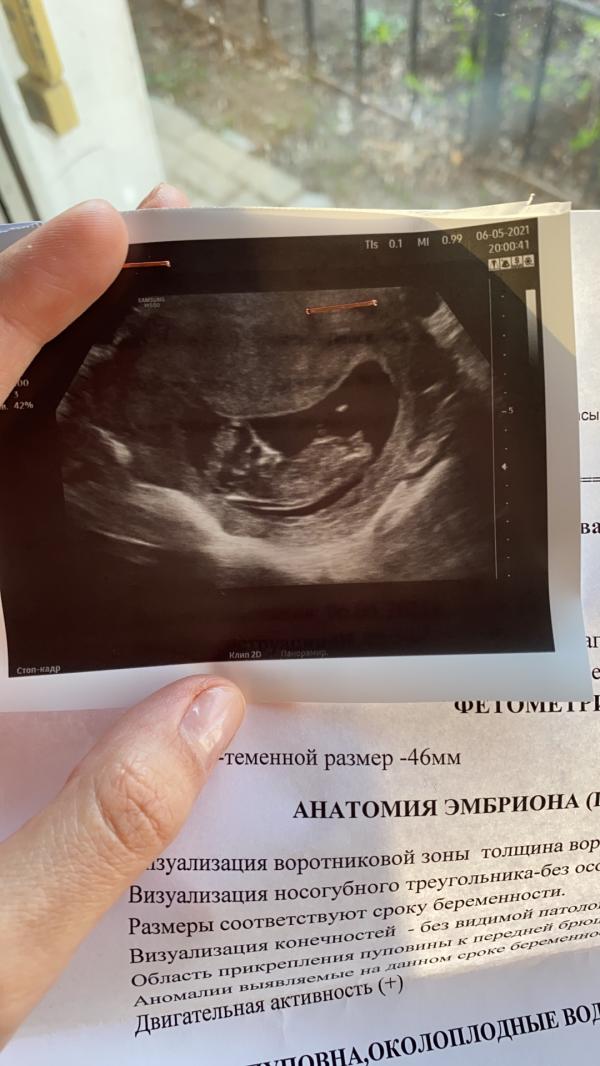

Охота поделиться со всеми, но пока в тайне оставим фотки главное близкие видели🥰 Ну, а пока я могу вести записи, мысли, ощущения здесь. По ощущениям первый триместр не было никакого токсикоза, ходила как и обычно. Может у всех по разному.